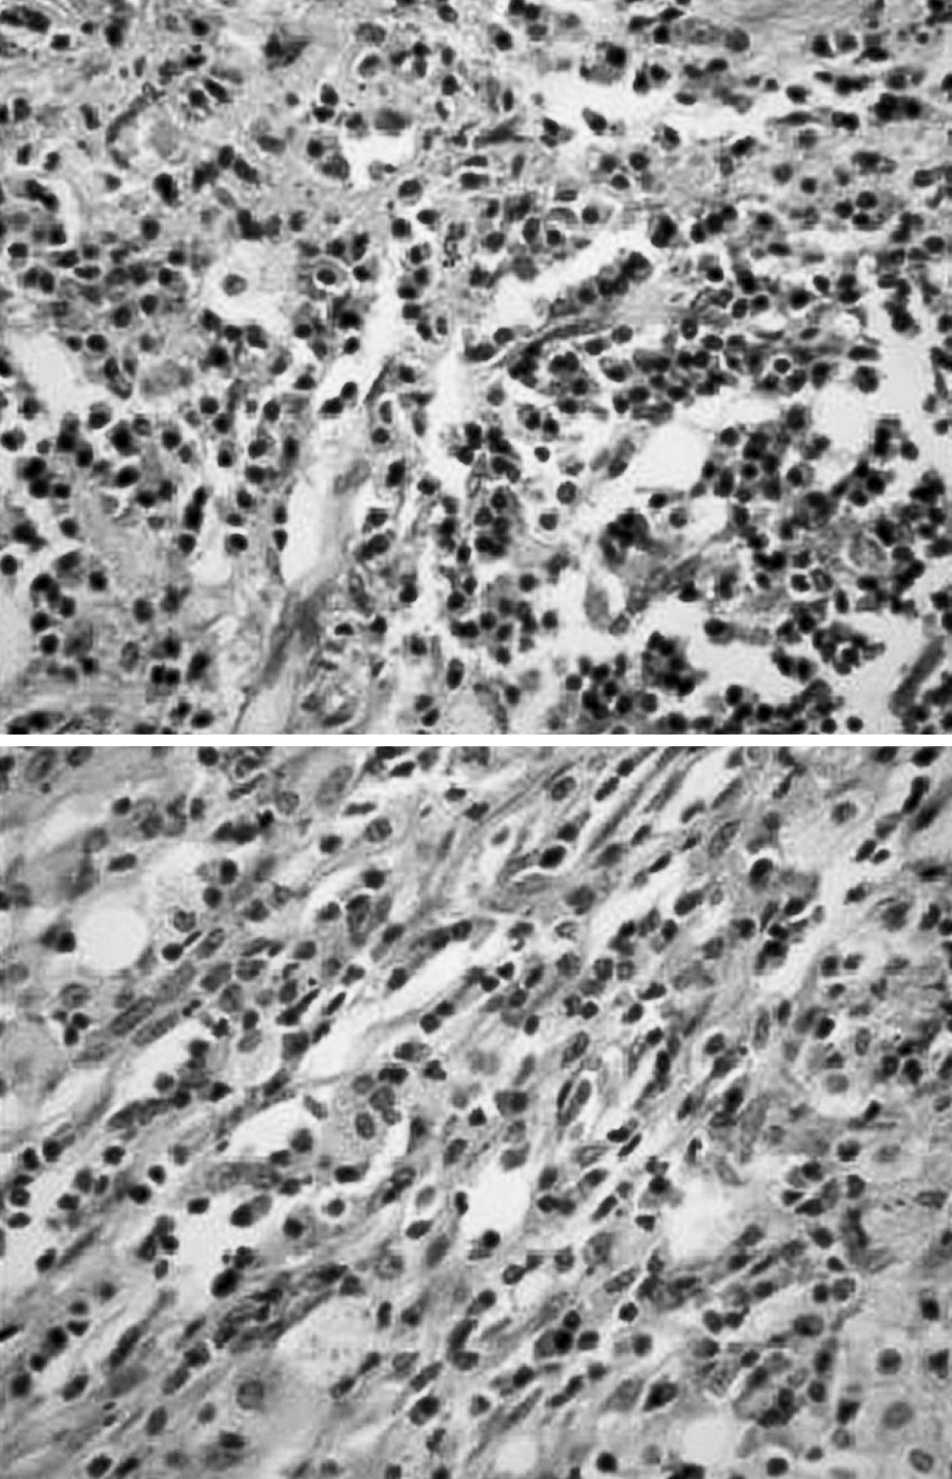

A los 13 meses de la intervención, el paciente acudió de nuevo a nuestro hospital por notarse una tumoración cervical y disnea a pequeños esfuerzos. A la exploración destacaba una tumoración submandibular derecha dura, adherida a planos profundos, de aproximadamente 3 x 4 cm de diámetro. La resonancia magnética puso de manifiesto una tumoración orofaríngea y nasofaríngea, con obliteración del espacio aéreo (fig. 2). Mediante biopsia incisional, se confirmó histológicamente que dicha lesión correspondía a un foco extrapulmonar del seudotumor (fig. 3). El tumor se comportó de forma agresiva infiltrando la porción cervical del esófago y la vía aérea, clínicamente manifestada como disfagia e insuficiencia respiratoria, por lo que requirió la realización de gastrostomía y traqueostomía permanente. En posteriores radiografías de control se detectó la aparición de nuevas masas pulmonares, una localizada en el lóbulo superior izquierdo y otra paramediastínica derecha. Se desestimó la opción quirúrgica y se inició tratamiento farmacológico con corticoides e inmunosupresores; el paciente respondió al tratamiento y se objetivó una disminución del tamaño de sus procesos tumorales.

Fig. 2. Resonancia magnética que muestra tumoración orofaríngea y nasofaríngea, con obliteración del espacio aéreo.

Fig. 3. Imágenes histológicas con tinción H-E (x40) de la lesión pulmonar (A) y de la lesión cervical (B), ambas similares, donde se observa proliferación heterogénea mesenquimal de predominio fibroblástico e inflamatorio a expensas de células plasmáticas y linfocitos maduros.